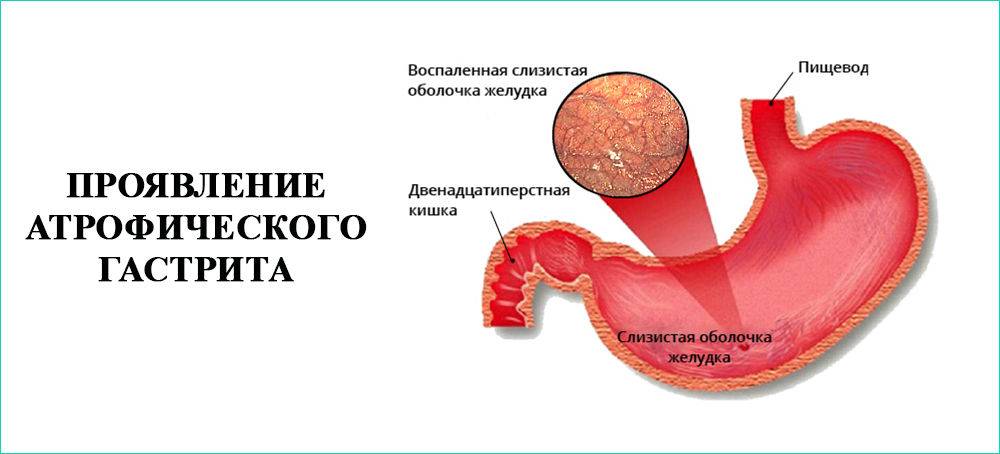

Информация и фотографии о хроническом гастрите и дуодените